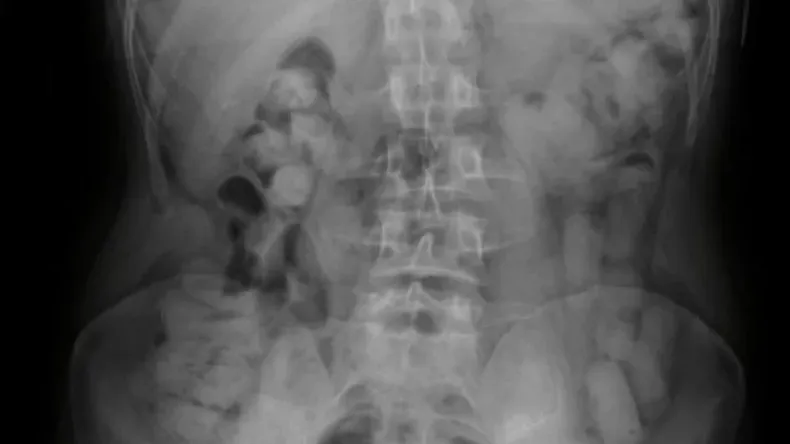

Tres jóvenes bolivianos fueron detenidos luego de que Gendarmería Nacional descubra que se habían tragado 235 cápsulas de cocaína.

Fue al subirse a ese micro que notaron que había tres hombres de nacionalidad boliviana y mostraban signos de haber ingerido cápsulas estupefacientes. Una radiografía lo confirmó.

Gendarmería Contabilizó 235 cápsulas que los jóvenes expulsaron cuando estuvieron detenidos e internados en el hospital por un día. En total, se trataba de 2 kilos, 554 gramos de cocaína.